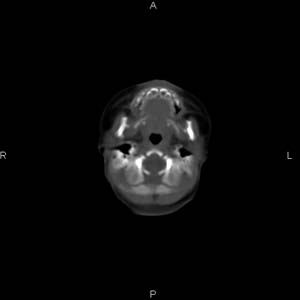

患者男,27天,出生后正常,今天中午在母亲怀里抱着吃奶在放下睡觉时发现后枕部慢慢出现一包块,来查头颅ct。无外伤史。包块内ct值47-51hu。请大家讨论。

皮下血肿,颅骨无缺如 ,颅缝无增宽。皮下血管破裂所因起。

头皮下血肿,局部枕骨略有凹陷

支持脑膜脑膨出,双侧侧脑室三角区周围脑白质对称性低密度影,考虑缺血缺氧性脑病或肾上腺性脑白质营养不良。

\"中午在母亲怀里抱着吃奶在放下睡觉时发现后枕部慢慢出现一包块,包块内ct值47-51hu。

颅骨无缺损,骨缝无增宽.支持头皮血肿(血管破裂)